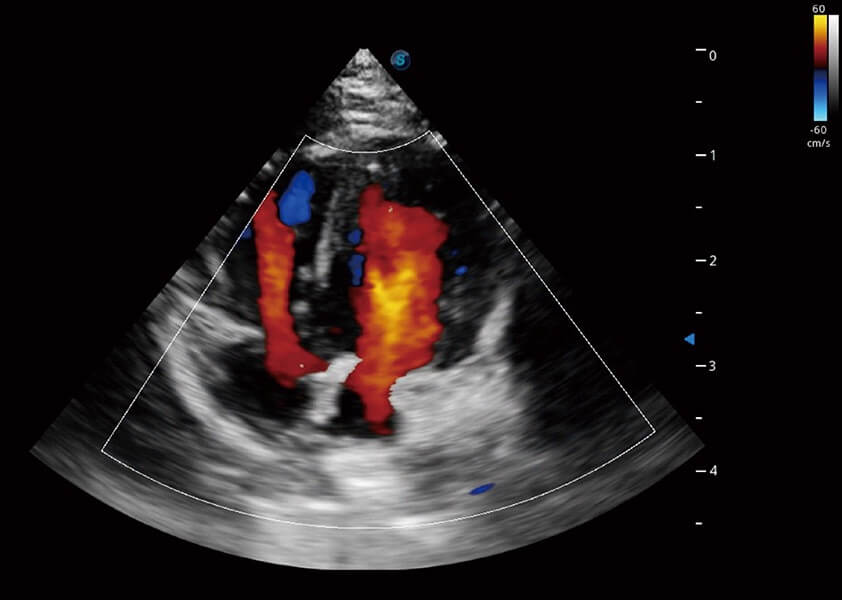

ProPet 60 作為一款高端臺(tái)式動(dòng)物超聲設(shè)備,為動(dòng)物醫(yī)生的日常診斷提供了一系列貼合動(dòng)物臨床需求、解決臨床實(shí)際問(wèn)題的高級(jí)成像功能。憑借全系列高清探頭,滿(mǎn)足醫(yī)生對(duì)腹部、心臟、生殖、淺表、肌骨等成像的所有需求,切實(shí)幫助您提升檢查效率,提高診斷信心。